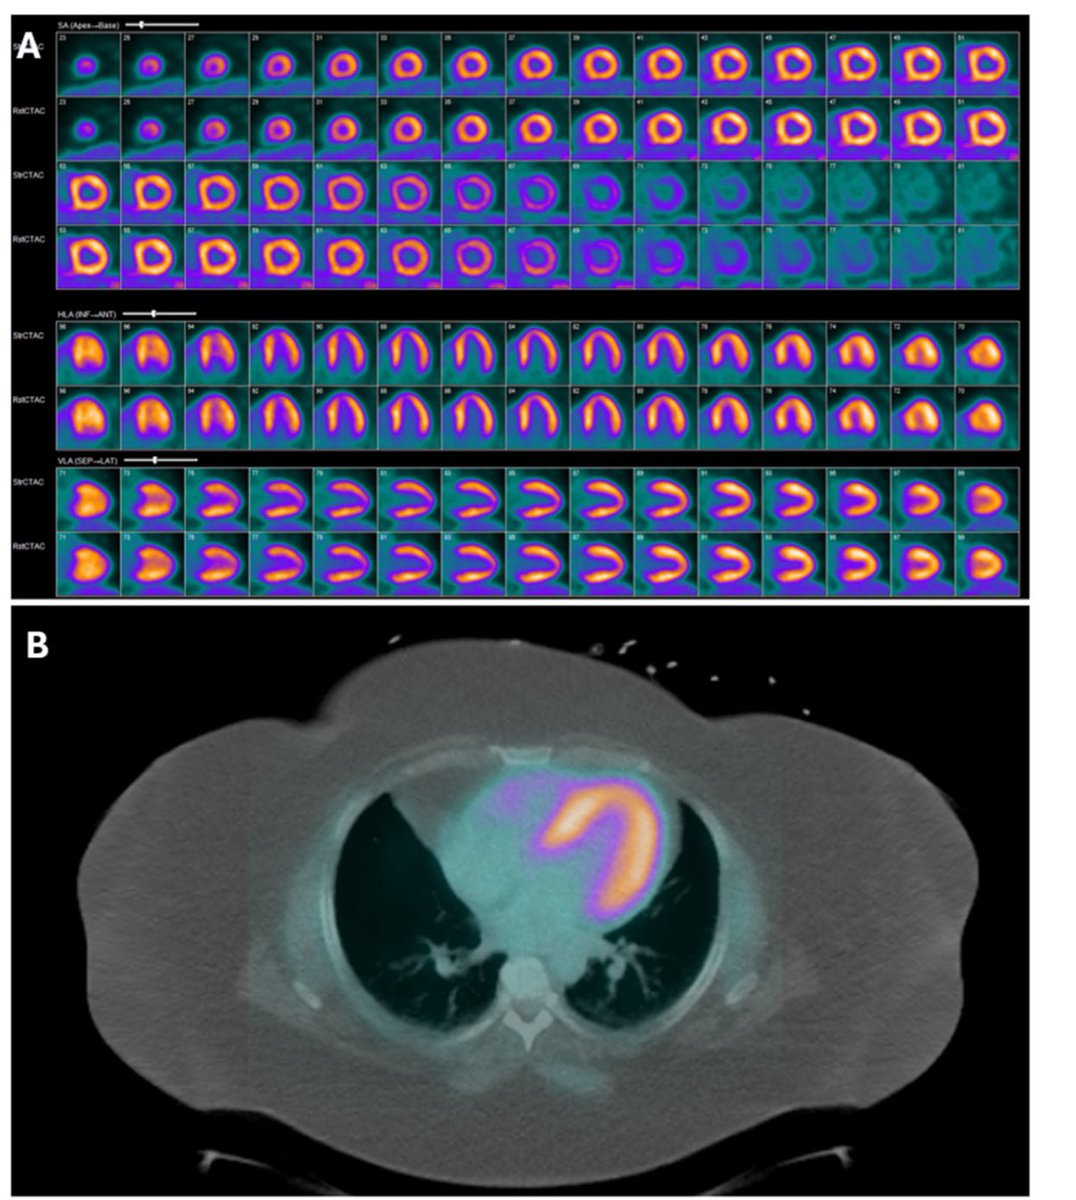

🚀 PET/CT is rocking in cardiology guidelines! ✅ Superior to SPECT for CAD & CMD ✅ MBF/MBFR for risk stratification ✅ Stronger role in #Endocarditis, #Sarcoidosis, #Amyloidosis & transplant vasculopathy European Society of Cardiology American Heart Association journalofnuclearcardiology.org/article/S1071-… ASNC Society Journal of Nuclear Cardiology

🚀 PET/CT is rocking in cardiology guidelines!

✅ Superior to SPECT for CAD &amp; CMD

✅ MBF/MBFR for risk stratification

✅ Stronger role in #Endocarditis, #Sarcoidosis, #Amyloidosis &amp; transplant vasculopathy